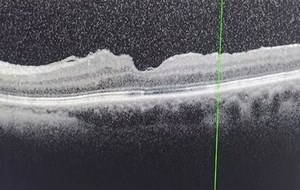

At eight weeks, OCT confirmed successful closure of the macular hole as shown in Figure 12. Despite this, the patient continued to experience central metamorphopsia that interfered with reading, a commonly reported persisting symptom despite macula hole surgery [4].

Figure 12: Macula OCT scan 8 weeks postoperatively [3].